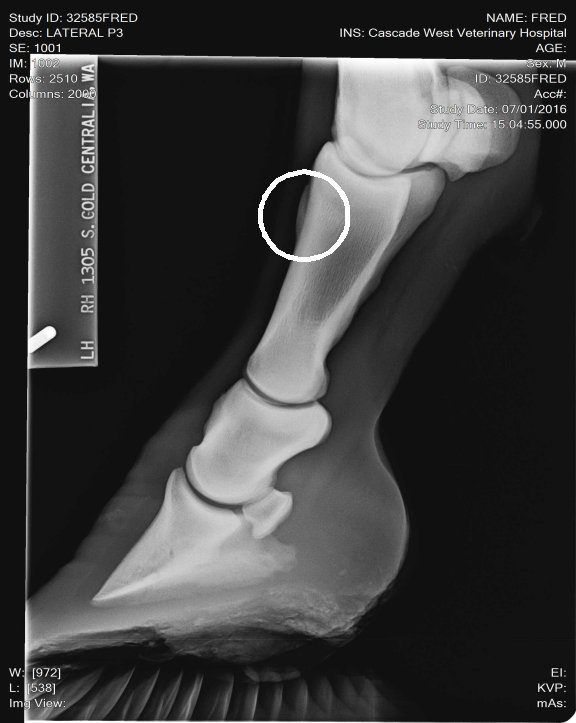

Location: Washington | Here is the correct spot circled!

Location: Lost in the swamps | My opinion these X rays don't look bad. I don't see any involvement in the joint spaces. I've seen a lot worse. He's got really long toes, you need to show your farrier these x rays and have him shorten and round his toes to quicken his break over is very important for horses dealing with ringbone. long toes create a lot of torque! This can also lead to lamine inflammation. The p-1 and p-2 is a low motion joint so it can actually fuse and the horse still have soundness. Your p2 and coffin joint is where you don't want any issues of ring bone. And I don't see any there. The upper pattern has some oddity near the seasmoid bone. Just curious did your vet mention anything? |